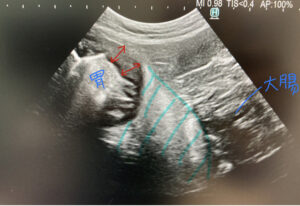

今回は「血を吐く」という主訴の、キャバリアの患者さんのエコー画像です。胃の壁が分厚くなっている(赤矢印)、周りの脂肪がより白く写っている(水色斜線の範囲)、このことから「胃に炎症があり、周りの脂肪にも炎症が伝わっている(脂肪が白くなることから)」ということがわかります。

またこの患者さんは、その胃炎の“原因”があると疑い、そこも含めて詳しく飼い主さんと方針を相談しました。